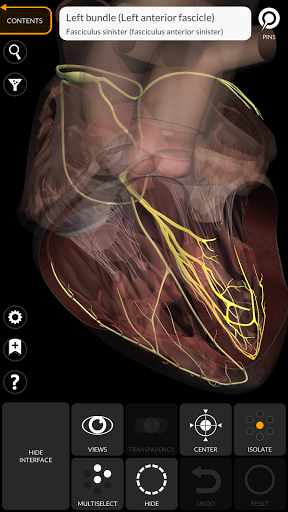

"Anatomy 3D Atlas" дозволяє легко та інтерактивно вивчати анатомію людини.

Завдяки простому та інтуїтивно зрозумілому інтерфейсу можна спостерігати кожну анатомічну структуру під будь-яким кутом.

Анатомічні 3D-моделі особливо деталізовані та мають текстури з роздільною здатністю до 4k.

• Серцево-судинна система

• Можливість приховування або ізоляції однієї чи кількох вибраних моделей

• Функція прозорості